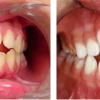

Diasteem

Diasteem – vahe esimeste hammaste vahel. Esineb 50%-l 6-8 aastastel lastel. Kuni 2 mm diasteemi puhul on, peale lateraalse intsisiivi ja silmahamba lõikumist, võimalik diasteemi iseeneslik sulgumine. Diasteem, mille suurus...